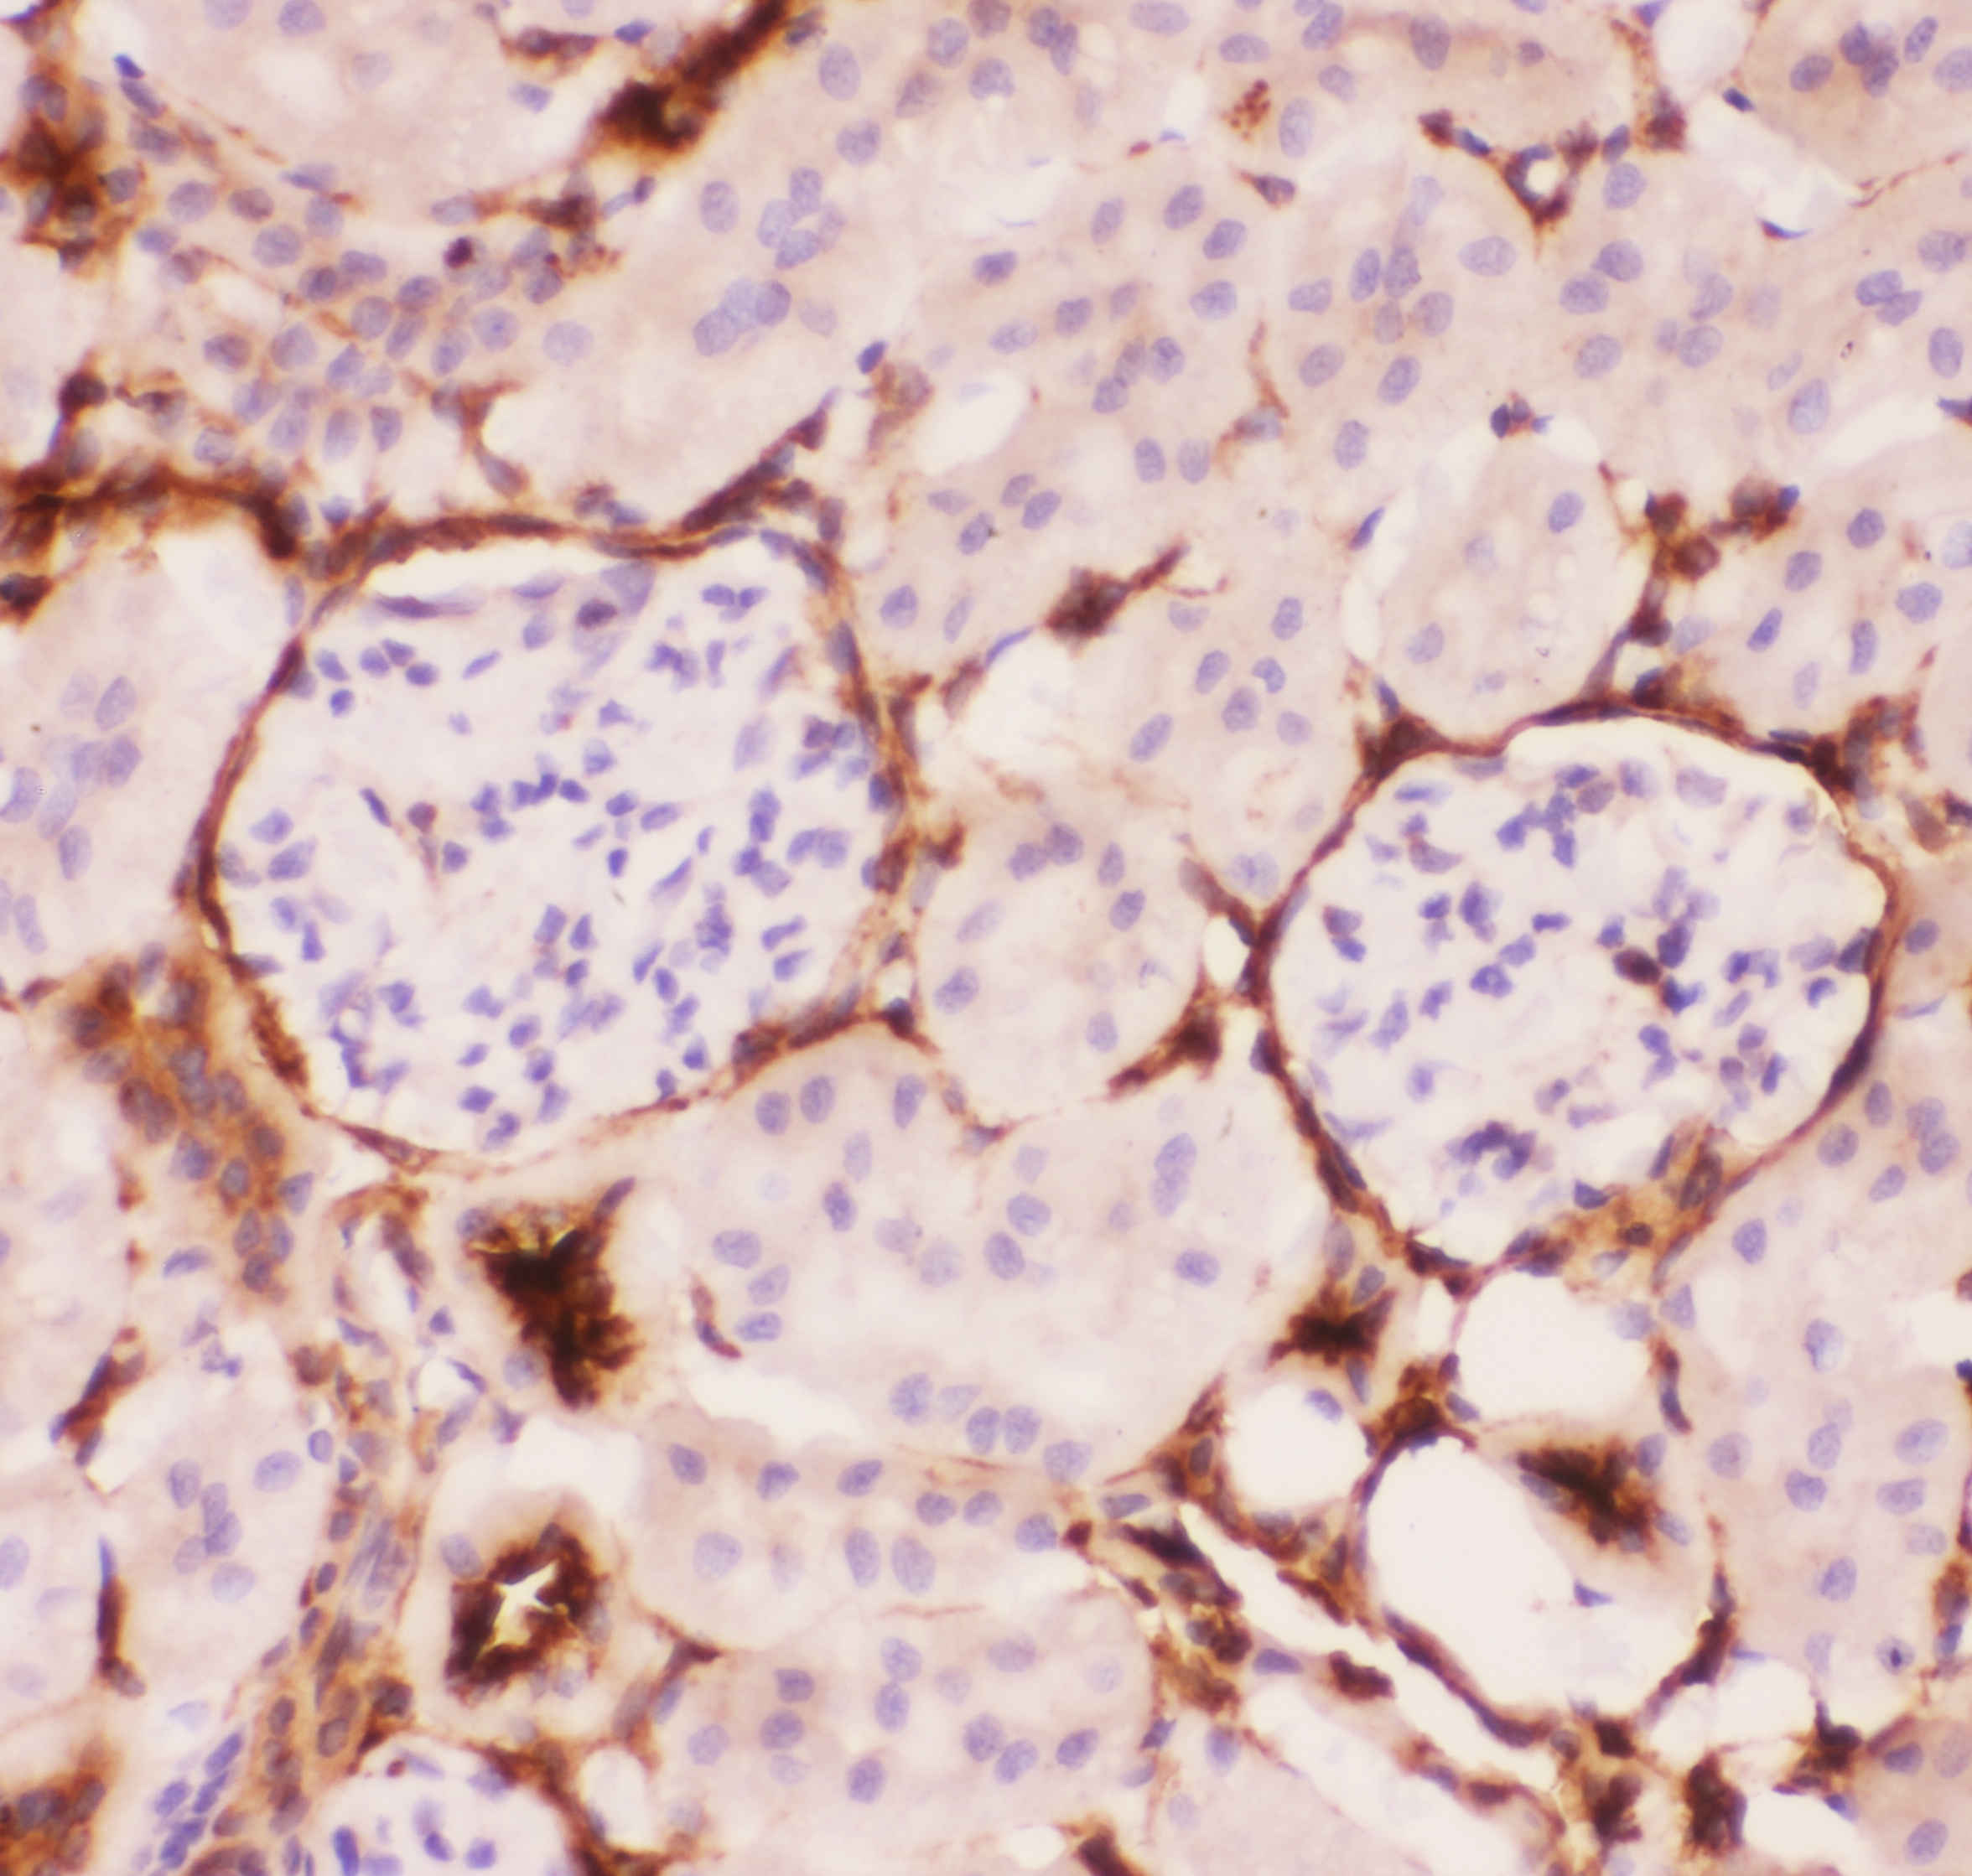

IHC analysis of P glycoprotein/ABCB1 using anti-P glycoprotein/ABCB1 antibody (PB0162).

P glycoprotein/ABCB1 was detected in a paraffin-embedded section of mouse kidney tissue. The tissue section was incubated with rabbit anti-P glycoprotein/ABCB1 Antibody (PB0162) at a dilution of 1:200 and developed using HRP Conjugated Rabbit IgG Super Vision Assay Kit (Catalog # SV0002) with DAB (Catalog # AR1027) as the chromogen.